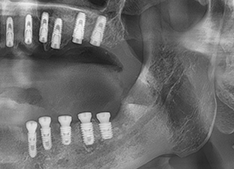

서울탑플란트 치료사례

어떠한 임플란트 케이스도 문제없이 치료가 가능합니다

Q2. 청주임플란트 시술은 어떤 과정을 거치나요?

A2. 임플란트 시술은 CT 촬영으로 잇몸뼈 상태를 확인한 뒤,

인공치근을 식립하고 치유 기간을 거쳐 보철물을 장착하는 과정으로 진행됩니다.

서울탑플란트치과는 3D 디지털 가이드 시스템을 사용하여

절개 범위를 최소화하고 빠른 회복을 유도합니다.